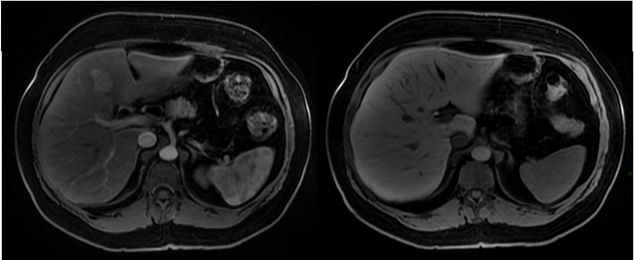

Mulher de 45 anos, sem história pessoal de câncer, foi submetida a exame de ressonância magnética do abdome superior com contraste venoso hepatoespecífico após achado de nódulo hepático incidental em ultrassonografia. Nas sequências pré-contraste, o nódulo apresentava discreto baixo sinal na ponderação T1 e discreto alto sinal na ponderação T2, ambas com supressão de gordura. Abaixo temos imagens nas sequências T1 em fase, T1 fora de fase, T1 pós-contraste (fase arterial) e T1 pós-contraste (fase hepatobiliar). As sequências pós-contraste mostram que o nódulo apresenta intenso realce arterial e hipossinal em relação ao parênquima na fase hepatobiliar.

I. Há queda de sinal na ponderação T1 fora de fase tanto no parênquima hepático como no nódulo do segmento IV hepático em relação à ponderação T1 em fase, sugerindo quantidade significativa de gordura intracelular no parênquima e no nódulo.